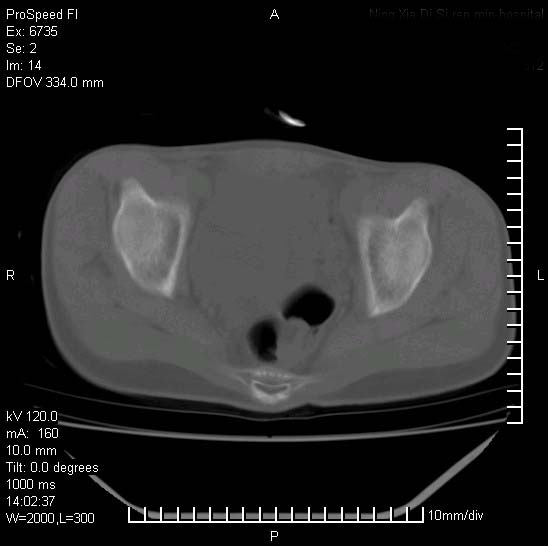

患者自诉胯部疼痛两年余,在当地服用中药,半月前至本院考虑骶髂关节结核,给予抗痨治疗。现发展至右下肢疼痛明显,活动受限,以膝关节处明显,拍膝关节平片无明显异常。

左侧骶髂关节面限局性骨破坏,边缘硬化关节腔见钙化物;不出外tb

右侧骶髂关节也有类似改变,只是较左侧轻,首先考虑强直性脊柱炎,不除外结核,建议作hla-b27检查。

典型强脊炎改变,髋关节亦有累及

符合强直性脊柱炎表现。